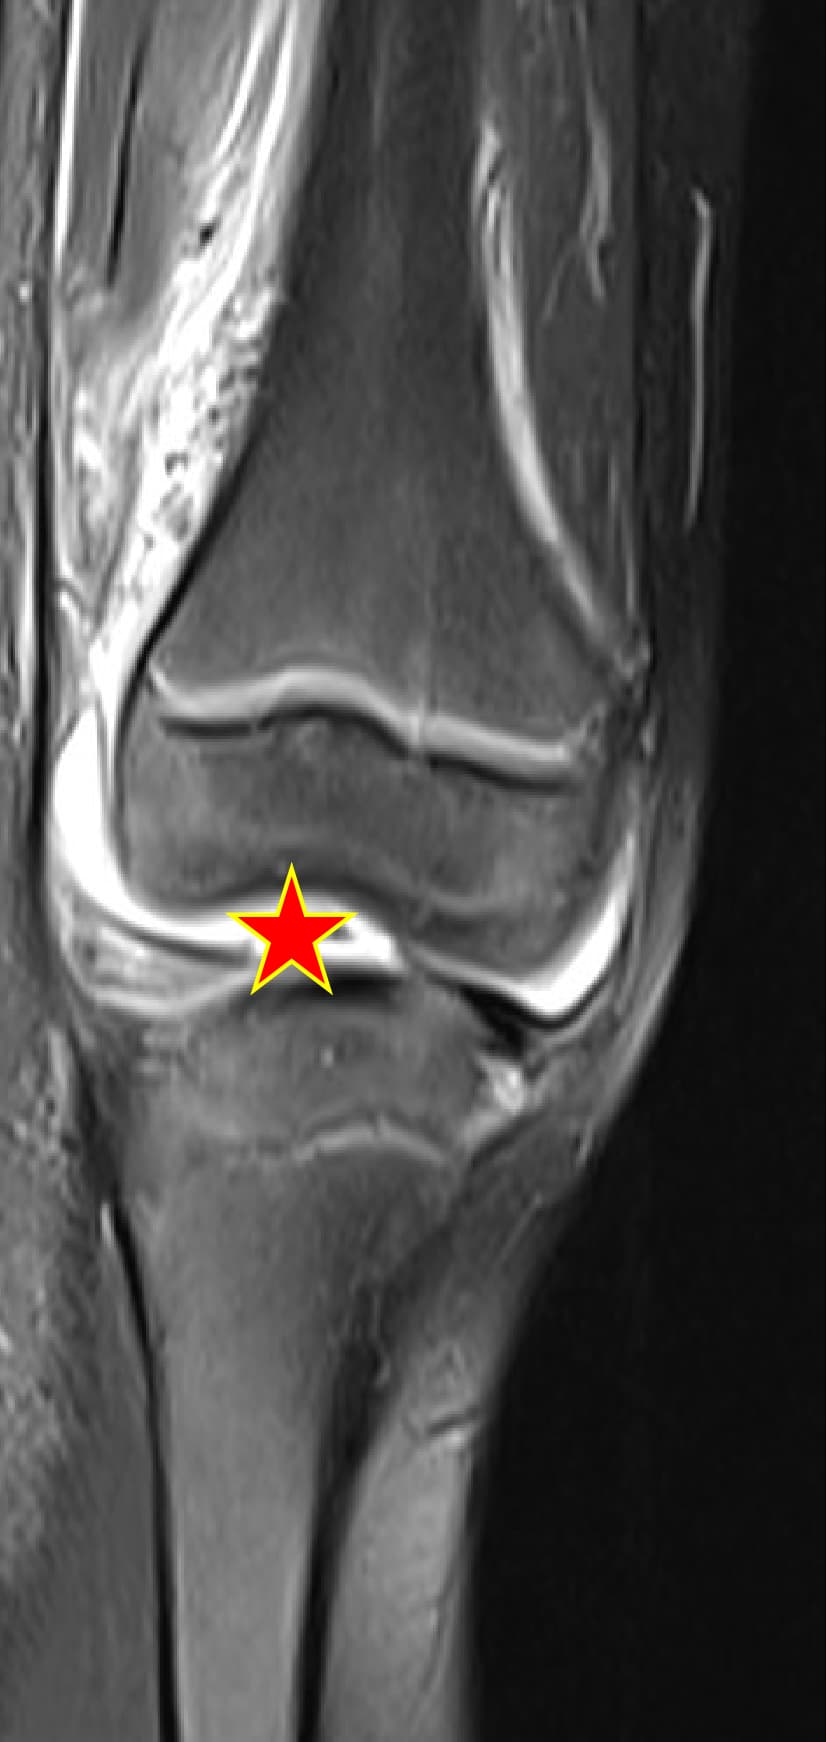

Septic arthritis cases